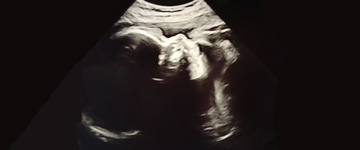

Zwangerschapskwalen en zwangerschapsziektes

De meeste vrouwen hebben tijdens hun zwangerschap last van zwangerschapskwalen. Misselijkheid en vermoeidheid zijn bekende zwangerschapskwalen. Die treden meestal in het eerste trimester op. In die fase is ook de kans op een miskraam het grootst. Sommige kwalen houden langer aan of komen later in de zwangerschap. Je kunt er veel last van hebben, ook al zijn zwangerschapskwalen ‘normaal’ en horen ze er nu eenmaal bij. Zwangerschapsziektes zijn helaas wat minder onschuldig. Die kunnen de gezondheid van de zwangere en de baby bedreigen.